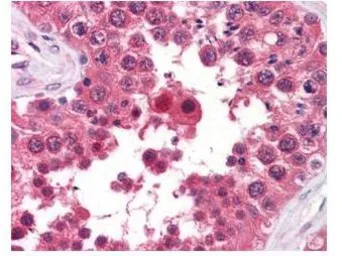

Anti-AHA-1 antibody [25F2.D9] used in IHC (Paraffin sections) (IHC-P). GTX48775

GTX48775 IHC-P Image

GeneTex's anti-AHA1 monoclonal antibody was used at a 5-10 μg/mL to detect AHA1 in the seminiferous tubule of human testis (40X) showing moderate staining. Leydig cells showed faint to moderate staining. Expression of AHA1 is reported in many epithelial and lymphatic tissues, with cytoplasmic localization. This antibody showed moderate cytoplasmic staining of a variety of epithelial tissues and lymphoid organs such as spleen and tonsil with minimal background staining. The image shows the localization of the antibody as the precipitated red signal, with a hematoxylin purple nuclear counterstain. Tissue was formalin-fixed and paraffin embedded.